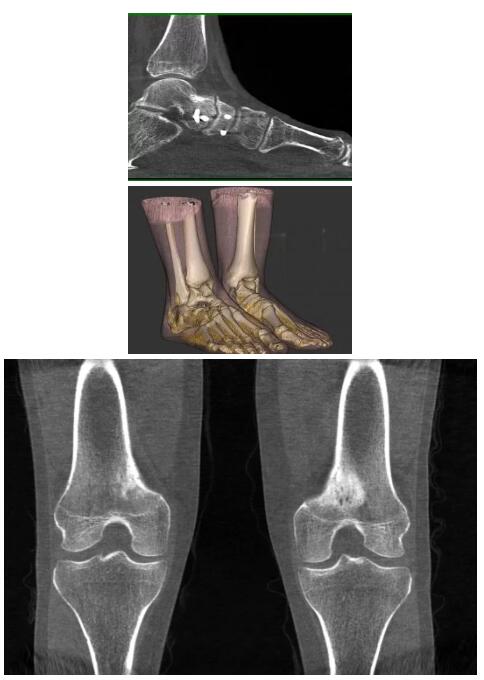

比如上面這款專用于足部和踝部掃查的CT成像系統(tǒng),患者在進行CT掃查時只需要站在上面即可,雙腳站或者單腳站都可以,當然,如果患者不是那么方便站著做完CT掃查,也可坐在上面。

這款CT掃查系統(tǒng)自帶屏蔽裝置,它的體積非常小,僅需要極小的空間即可,并不像常規(guī)CT那樣需要一間單獨的檢查室。此外,這種CT掃查的速度非???,僅需30秒左右可以完成檢查,輻射劑量相對常規(guī)的CT要少許多,尤其適合醫(yī)院的骨科使用。

而患者站著做足部或者踝部做CT檢查還有個好處是,可以檢查患者在負重的情況下,骨關節(jié)的真實情況,而躺著做CT掃查時未必能看出來。負重CT掃查特別是對于受傷的運動員或者舞蹈員來說意義更大,能夠更準確地評估傷情,幫助他們盡早復原。

以上介紹的CT均來自國外同一家公司,這些CT均配置了可視化軟件,可以進行切片、3D重建以及大型CT附帶的所有典型的操作功能。

以下是這些“特立獨行”的CT所拍出來的圖像: